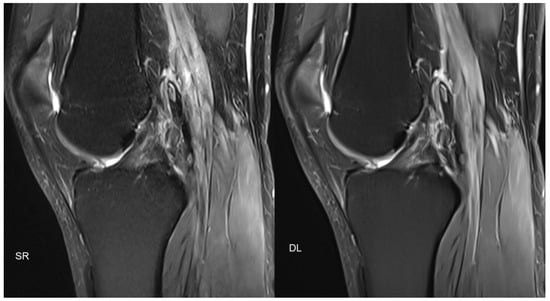

- Recht, M.P.; Zbontar, J.; Sodickson, D.K.; Knoll, F.; Yakubova, N.; Sriram, A.; Murrell, T.; Defazio, A.; Rabbat, M.; Rybak, L.; et al. Using Deep Learning to Accelerate Knee MRI at 3 T: Results of an Interchangeability Study. Am. J. Roentgenol. 2020, 215, 1421–1429. [Google Scholar] [CrossRef]

- Hammernik, K.; Klatzer, T.; Kobler, E.; Recht, M.P.; Sodickson, D.K.; Pock, T.; Knoll, F. Learning a variational network for reconstruction of accelerated MRI data. Magn. Reson. Med. 2018, 79, 3055–3071. [Google Scholar] [CrossRef]